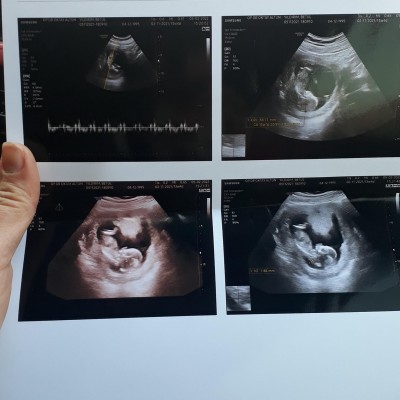

Benimde 13 haftalık şuan 3 gün sonra gititn doktor kız dedi ama değişir mi bilmiyorum çünkü ortason var bakarmisin

image